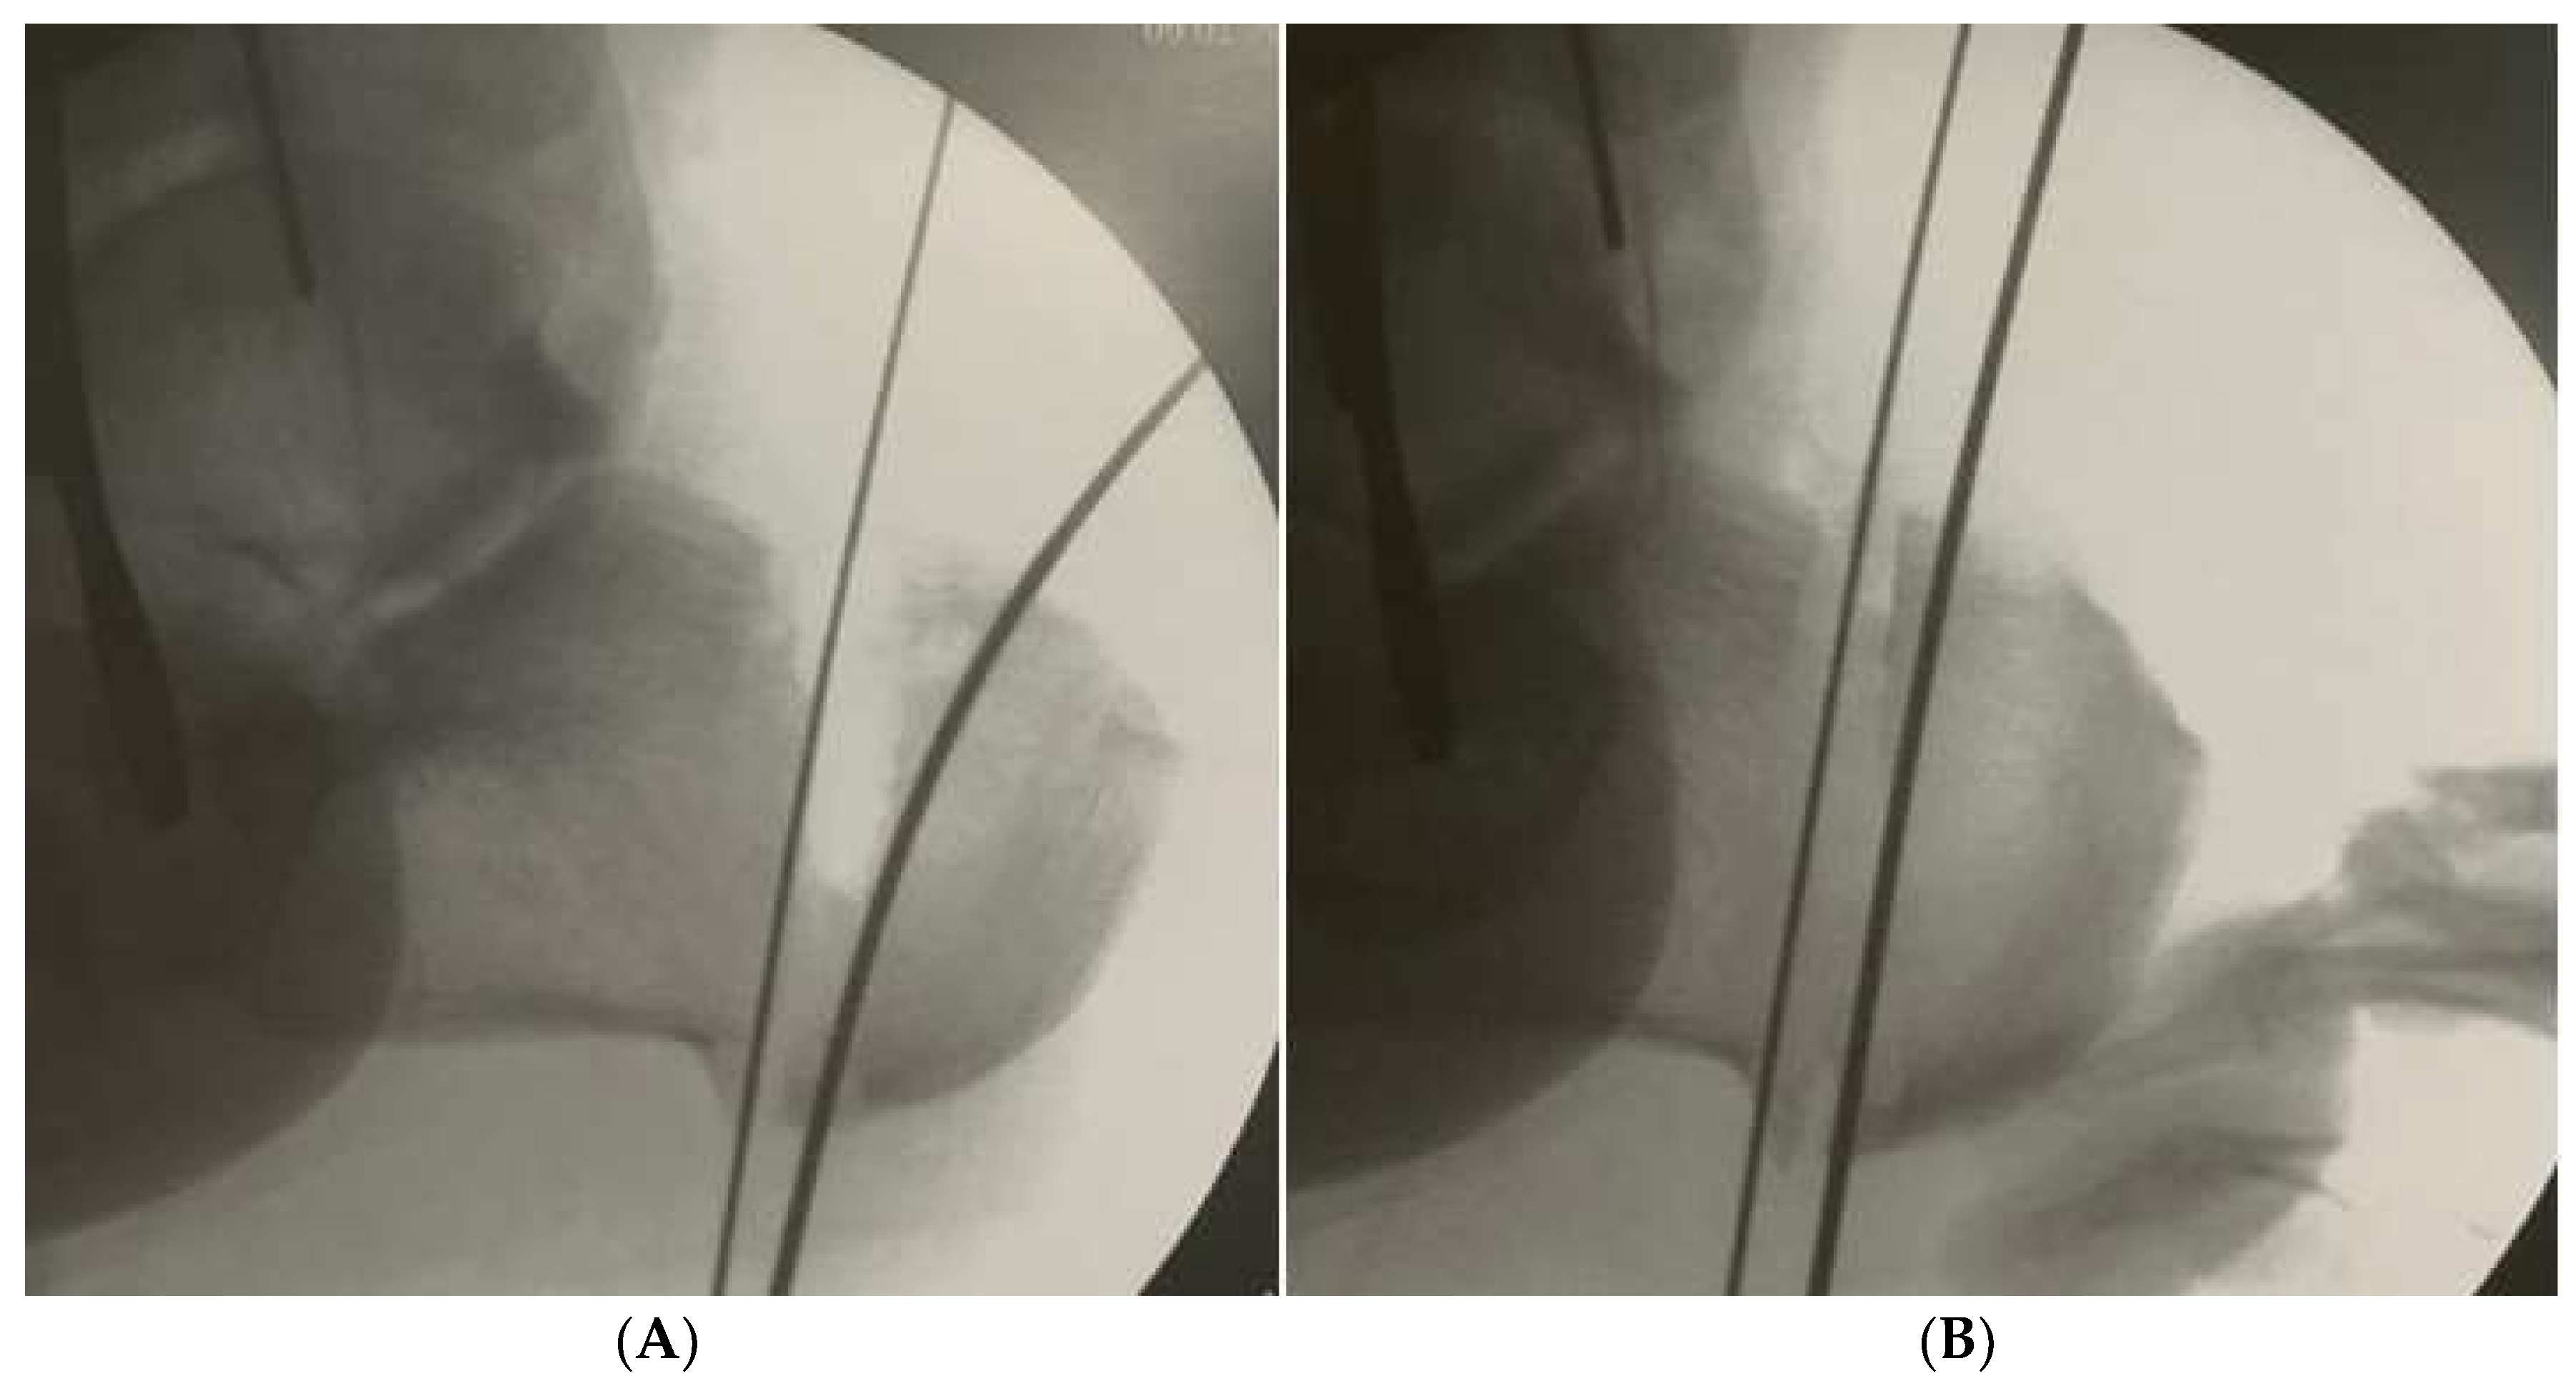

A lateral portal is made, a 4.3 mm burr inserted (using a self-irrigated low-speed high-torque drill), and a windshield wiper movement performed between both k-wires to remove all the lateral, dorsal and plantar bone. The movement should be continuous to allow a more uniform amount of bone to be removed. More dorsal bone is removed if the cavus is due to high calcaneal pitch, and more lateral bone if the varus aspect is more important (Figure 2). A 20 mm/2.2 mm Shannon burr is inserted and the medial cortical bone transected. Screw fixation parallels open techniques and the reduction can be verified in both lateral and axial views.

Figure 2. (a) Dorsal base closing wedge resected according to preoperative planning. (B) Dorsal base wedge closure.